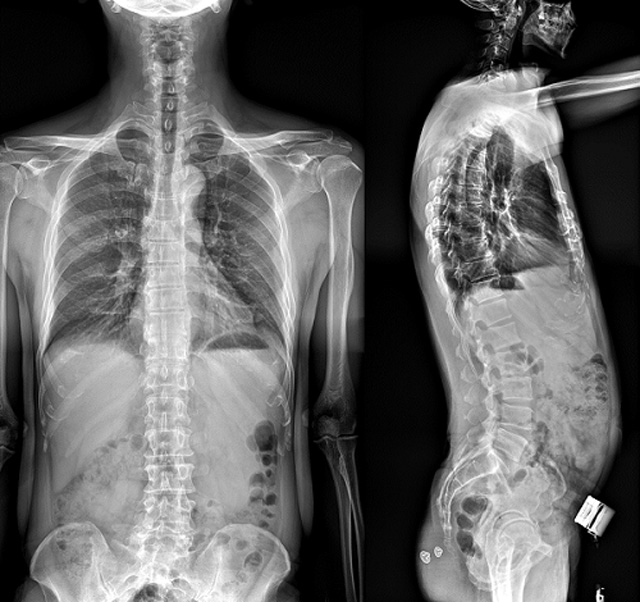

(7)全身拼接功能對(duì)有較大尺寸全脊柱拼接圖接桂成金下股分成幾次拍攝,再經(jīng)過(guò)秋件開(kāi)在骨科開(kāi)展的全脊柱畸形矯治工作中,雖然CT. MRI也能獲取全脊柱影像,接圖像,以便于長(zhǎng)度、角度、力線(xiàn)等測(cè)量和察脊柱在重力情況下但不能進(jìn)行立位檢查,無(wú)法觀(guān)全景觀(guān)察。全身拼接功能是高等級(jí)DR攝取患者立位全下的功能狀態(tài)圖像,因此采用動(dòng)態(tài)醫(yī)院特別看重的動(dòng)態(tài)DR功能之一。注:圖中Cobb脊柱正側(cè)位圖像是首選的檢查方法角度的大小是反映側(cè)彎嚴(yán)重程度的一個(gè)標(biāo)準(zhǔn)。